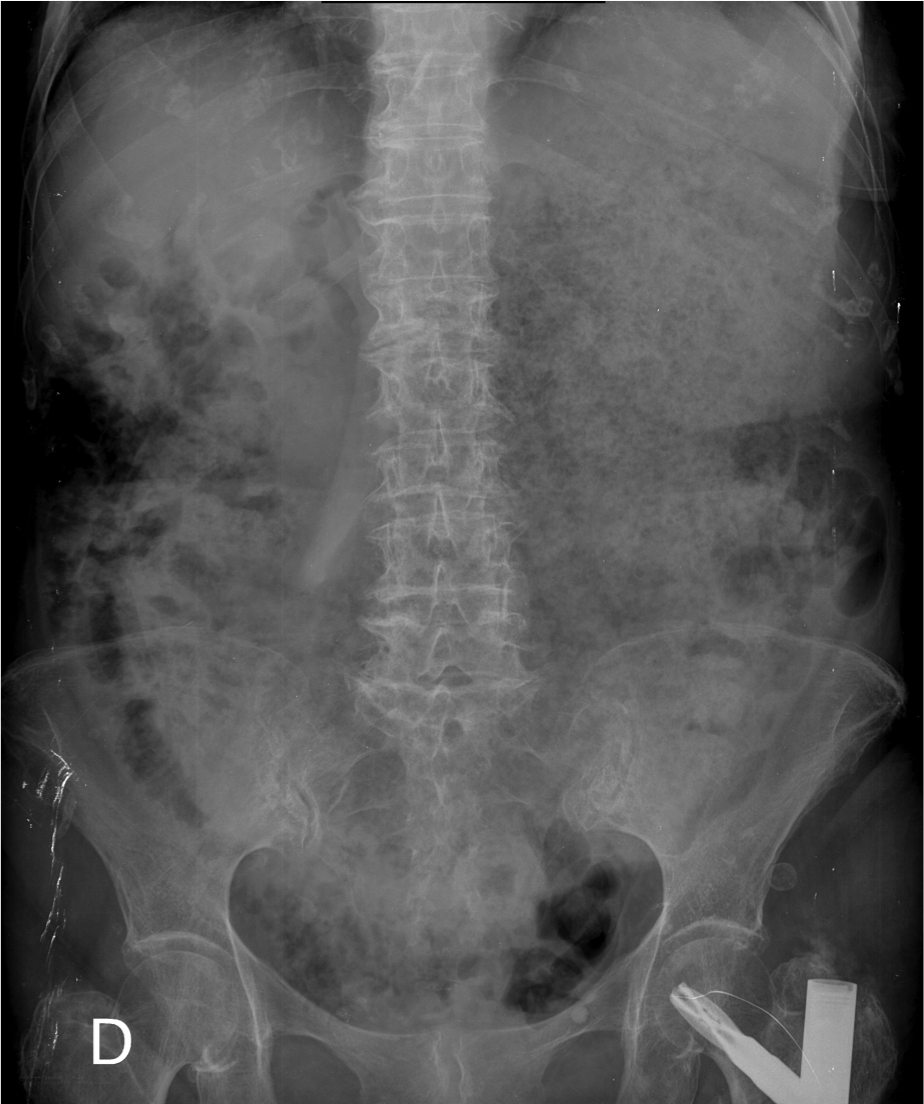

rx

Rx de Tórax 2P: llama la atención la cámara gástrica dilatada con abundante contenido con nivel hidroaéreo.

Otro caso: 1) Neumobilia + Dilatación de la cámara gástrica 2) Litiasis bilar + vesícula con proceso inflamatorio 3) Fístula vesiculo entérica 4) Dilatación de la cámara gástrica por obstrucción.